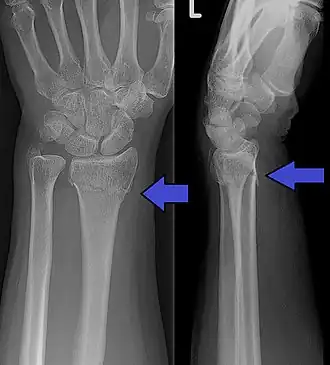

Collesfractuur met ook nog een fractuur van de processus styloides ulnae zichtbaar.

De term collesfractuur wordt gebruikt voor een extra-articulaire (dat wil zeggen, binnen twee centimeter van maar buiten het polsgewricht gelegen) breuk in het distale eind van het spaakbeen. Hierbij is er per definitie een hoekstand naar achteren, tussen het distale gedeelte (nabij de pols) ten opzichte van het proximale spaakbeen (richting de elleboog).